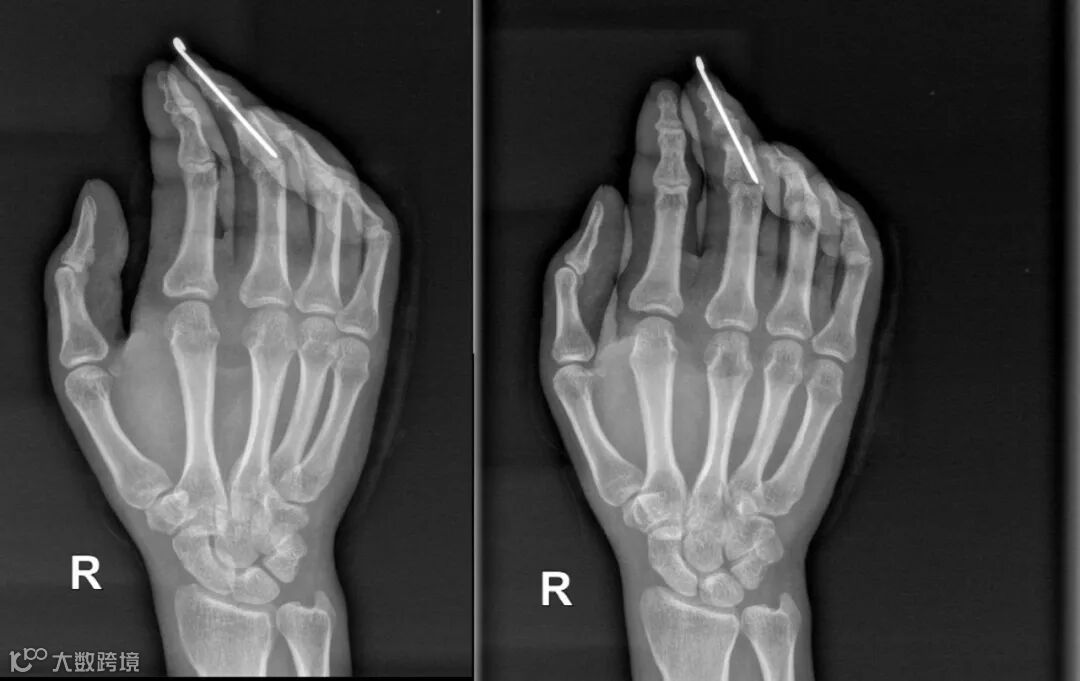

立即送手术室急诊手术,由覃育接主刀、陆春、孙华胜和庞聪作助手,为温师傅左拇指骨折复位,用针内固定,缝合修复断裂的肌腱,将神经和血管吻合修复。手术历时2个半小时,接上后左手大拇指指端毛细血管反应良好,颜色红润。

术后经过2周的治疗,温师傅的断指伤口已愈合,指端血运行良好,便拆线出院,医生叮嘱温师傅要注意患指适度进行功能锻炼,禁止持物、负重及剧烈活动,以防骨折内固定物松动或折断,定期门诊复诊,每月复查1次X光片,骨折愈合后再取出骨折内固定物。